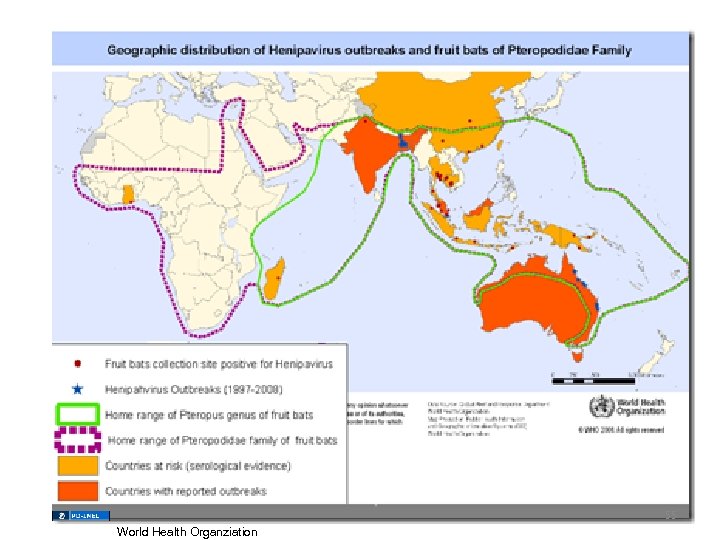

Henipah(Nipah) Virus Encephalitis • • 1998 - 1999 Malaysian pig farmers and health care workers 200 cases Transmission – Secretions from pigs, fruit bats – Human to human? – CDC • Bangladesh Bans Sale of Palm Sap After an Unusually Lethal Outbreak – New York Times DONALD G. Mc. NEIL Jr. Published: March 21, 2011 54

55 World Health Organziation